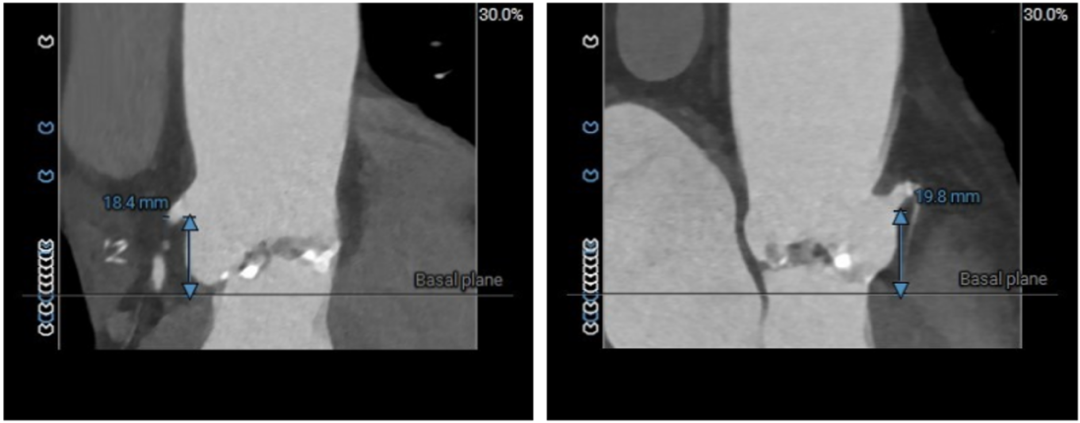

图3. 左冠高度:18.4mm  右冠高度:19.8mm